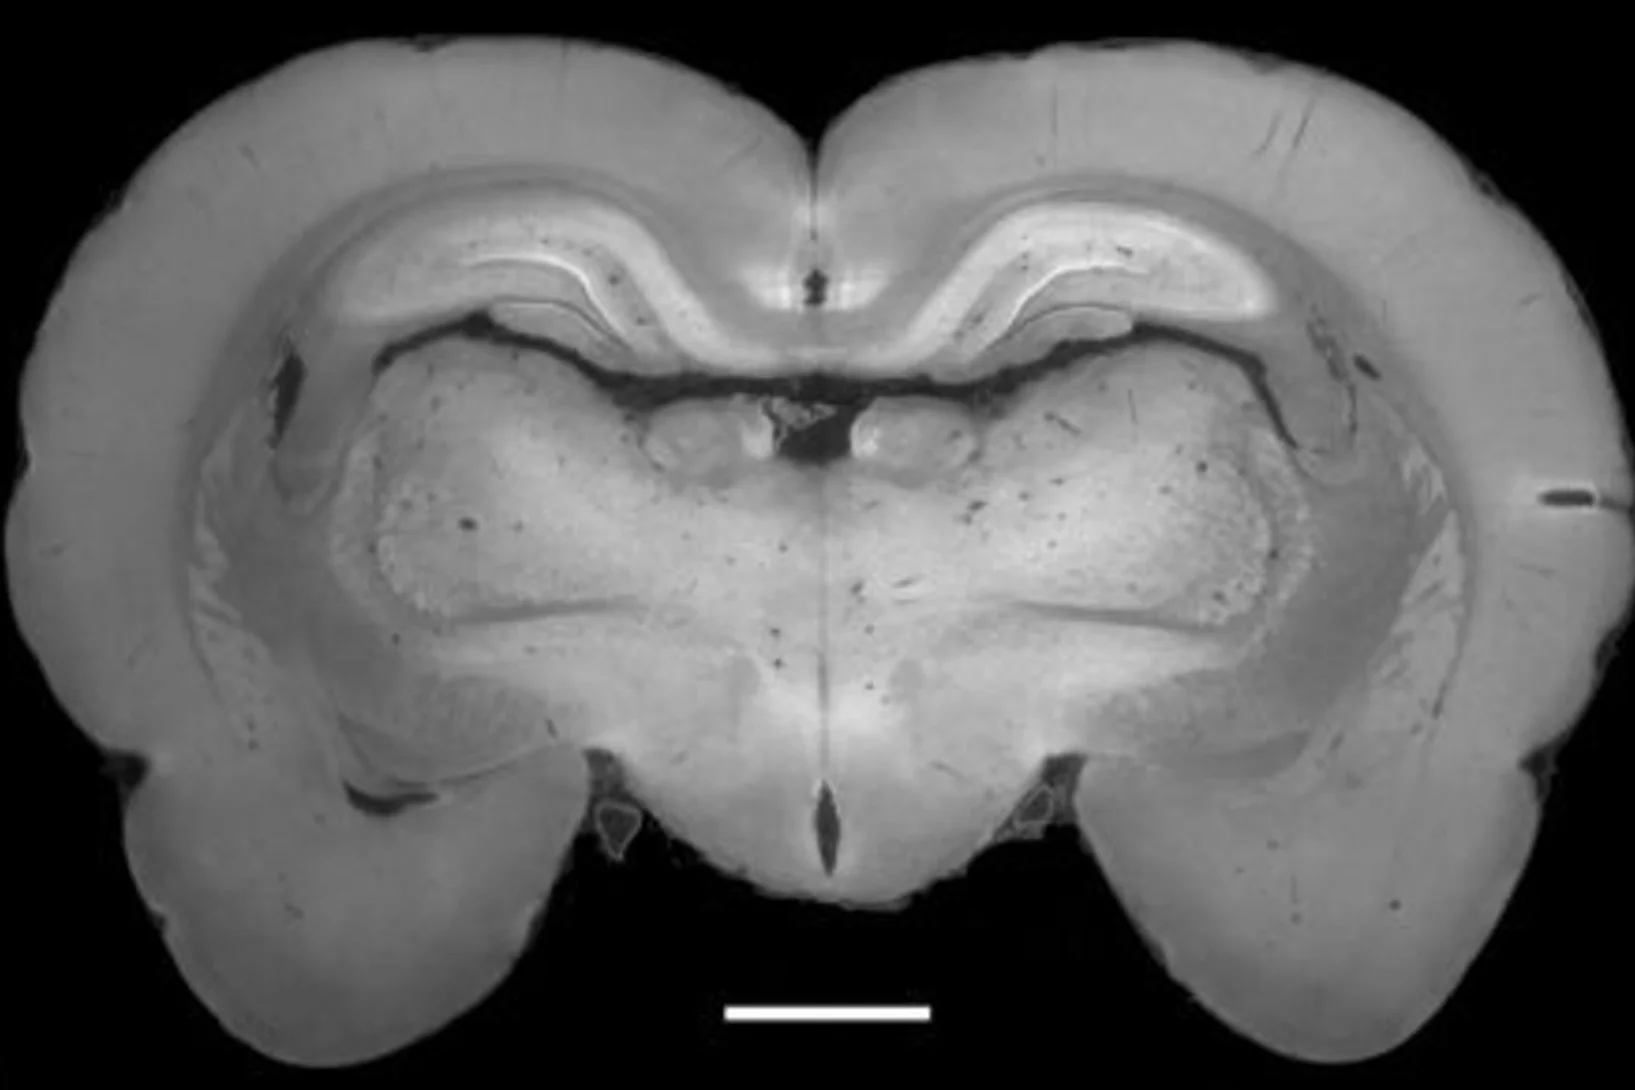

cross-section of the brain of a rat

X-ray methods help to understand brain disorders better

An international team of researchers from Denmark, Germany, Switzerland and France has developed a new method for making detailed X-ray images of brain tissue, which has been used to make the myelin sheaths of nerve fibres visible. Damage to these protective sheaths can lead to various disorders, such as multiple sclerosis. The facility for creating these images of the protective sheaths of nerve cells is being operated at the Swiss Light Source (SLS), at the Paul Scherrer Institute.